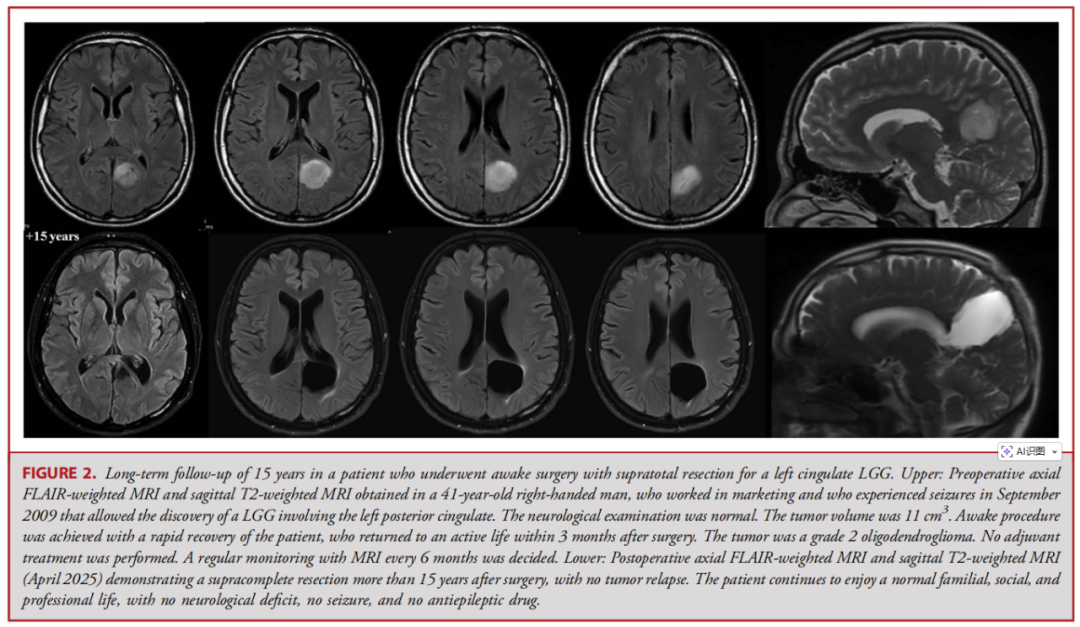

左侧扣带回低级别胶质瘤患者清醒手术超全切除后的15年长期随访。上图:术前MRI。下图:术后15年以上MRI,显示肿瘤超全切除,无复发迹象。患者目前仍保持正常的家庭、社会及职业生活,无神经功能缺损、无癫痫发作,未服用抗癫痫药物。